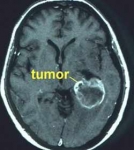

No sólo se conoce mejor la biología de la célula tumoral, sino también el medio ambiente en el que esta célula crece. Así, se han desarrollado fármacos cuyo mecanismo de acción se dirige a bloquear la producción de vasos sanguíneos que nutran al tumor (fármacos antiangiogénicos) de manera que las células tumorales mueren porque no pueden alimentarse.

Otro de los avances recientes es la aparición de la nanotecnología aplicada a la ingeniería farmacológica. Según explica el experto, se han desarrollado fármacos que han entrado en uso este mismo año en Europa, y que a partir de una molécula conocida y añadiendo nanopartículas a la misma, mejoran su perfil de eficacia y toxicidad. Este es un campo recién abierto que tiene enormes posibilidades para lograr una posible cura del cancer.